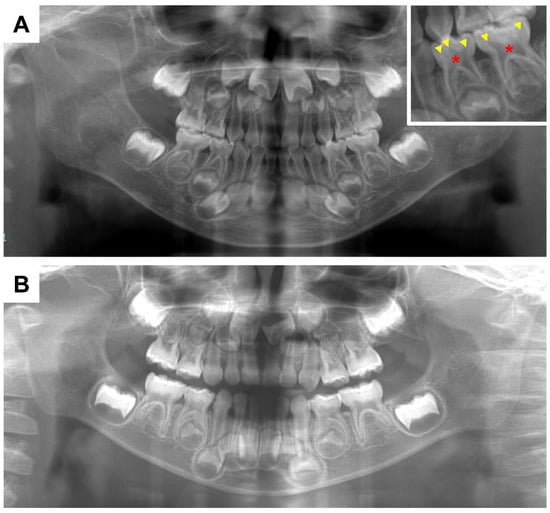

- Wato, K.; Okawa, R.; Matayoshi, S.; Ogaya, Y.; Nomura, R.; Nakano, K. X-linked hypophosphatemia diagnosed after identification of dental symptoms. Ped. Dent. J. 2020, 30, 115–119. [Google Scholar] [CrossRef]

- Okawa, R.; Hamada, M.; Takagi, M.; Matayoshi, S.; Nakano, K. A Case of X-Linked Hypophosphatemic Rickets with Dentin Dysplasia in Mandibular Third Molars. Children 2022, 9, 1304. [Google Scholar] [CrossRef]